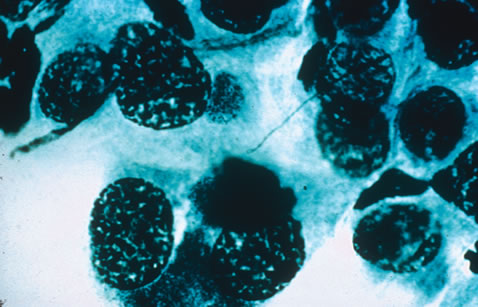

Any cell type may be infected, appearing larger than normal (cytomegalic) and demonstrating eosinophilic intranuclear “owl's eye” and smaller intracytoplasmic viral inclusion bodies, which are better seen with Giemsa or Papanicolaou's stains (Fig. 8). Histologic examination of tissue specimens, including bronchoalveolar lavage fluid and urine, may be useful for diagnosis.